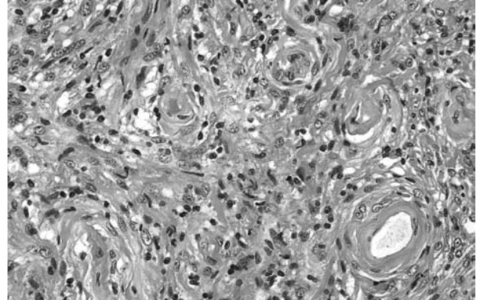

A 3-week-old girl is brought to the emergency department by her mother, who says her daughter has suddenly developed a large, tense bulge on the top of her head and a fever. The mother also notes that the patient has become more irritable and has not been feeding well. Although her mother received limited prenatal care, the child was born at 38 weeks’ gestation via spontaneous vaginal delivery without complications. The patient undergoes lumbar puncture, and a Gram stain of cerebrospinal fluid is shown in the image. Which of the following best characterizes the disease-causing agent in this patient?

(E) Gram-positive cocci, b-hemolytic, bacitracin-resistant 革兰氏阳性球菌,β溶血,杆菌肽耐药

该患者的表现高度怀疑细菌性脑膜炎。与年龄较大的儿童或成人(颈项强直)相比,新生儿的临床症状(发热、易激惹、嗜睡、喂养不良)无特异性。新生儿脑膜炎的最常见原因是B族链球菌,特别是无乳链球菌,这是一种存在于链中的β -溶血性革兰阳性球菌。与A组相比,无乳链球菌对杆菌素具有抗性。这种细菌的感染发生在阴道分娩期间,因为40%的女性是胃肠道和阴道内这种细菌的无症状携带者。大肠埃希菌和单核细胞增生李斯特菌是3个月大婴儿脑膜炎的第二和第三大常见病因。

正确答案:E